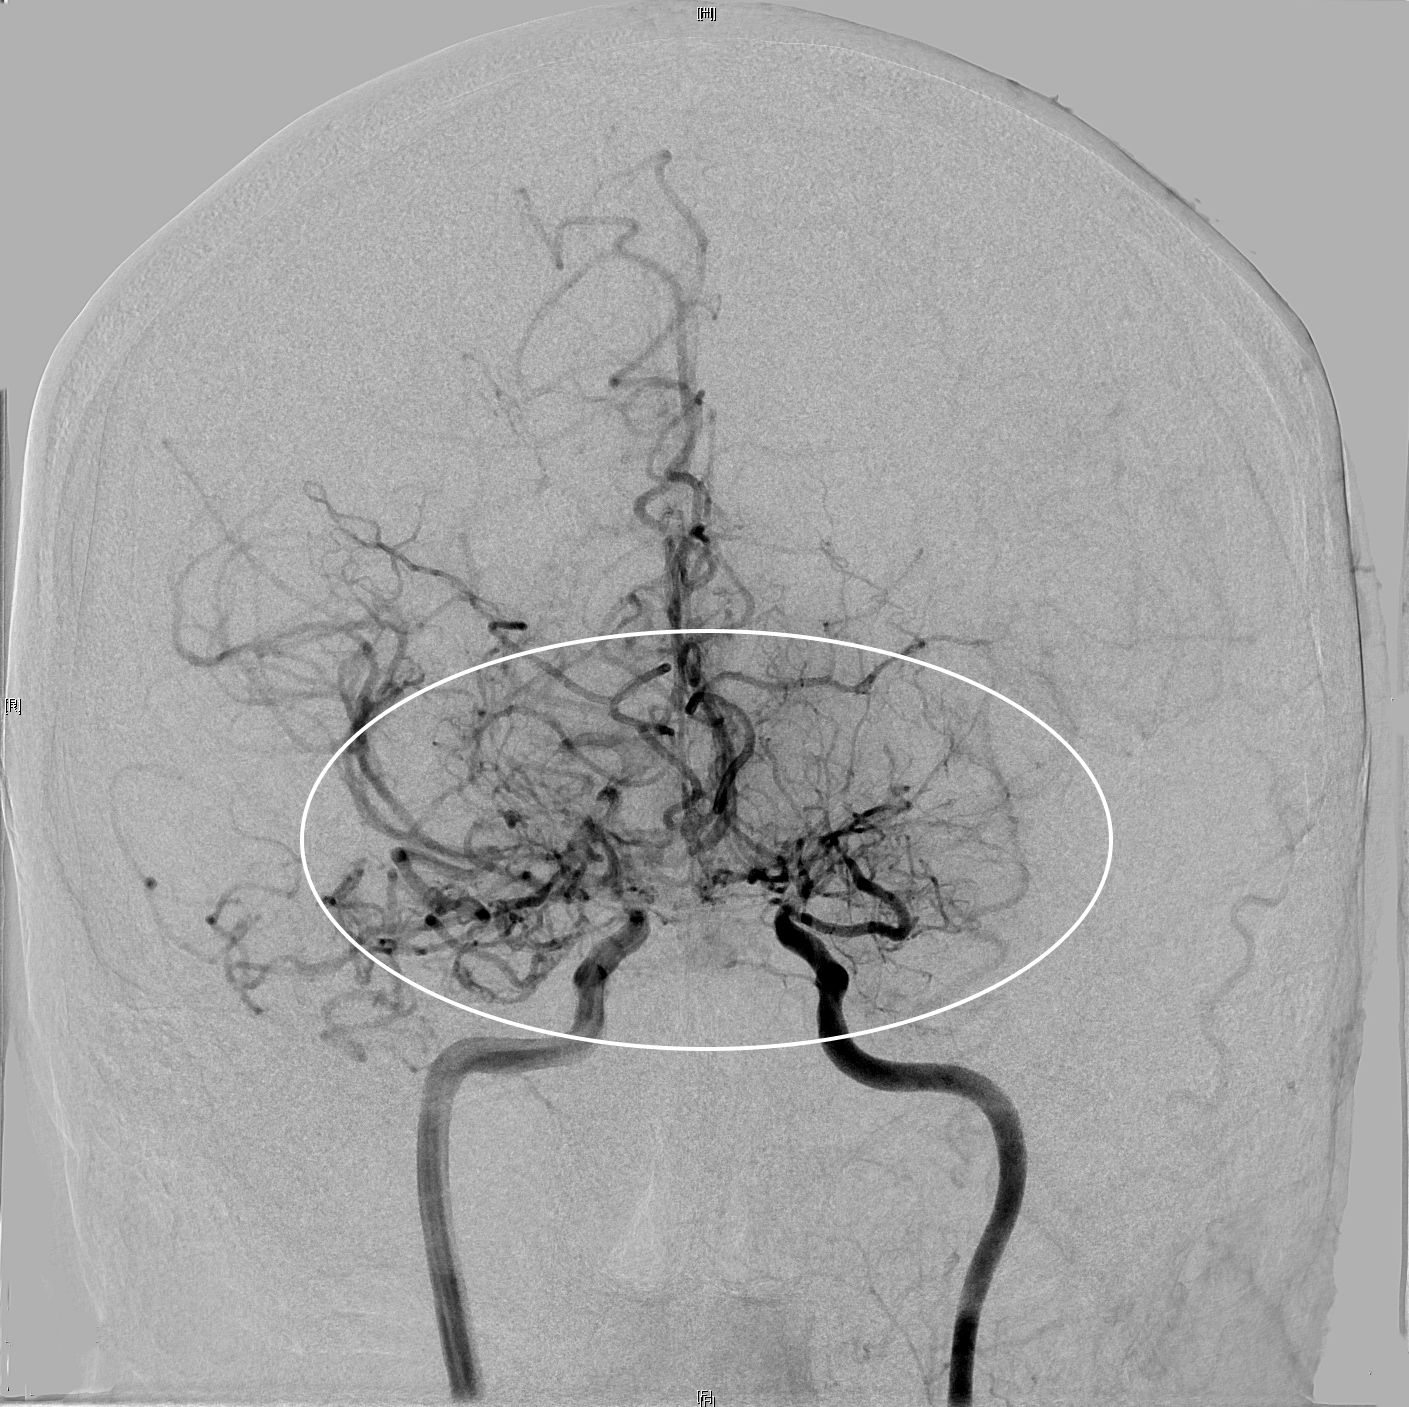

Bei Moyamoya handelt es sich um eine seltene Erkrankung, die zu Gefäßverschlüssen der großen Gehirnarterien führt. Die Krankheit kann bereits im Kindes- und jungen Erwachsenenalter auftreten und mit schwerwiegenden Folgen für die Betroffenen einhergehen, wie etwa wiederkehrenden Schlaganfällen. Die Ursache der Erkrankung ist bis heute noch ungeklärt: Genetische Faktoren, Umwelteinflüsse oder auch eine lokale Entzündung im Bereich der Gefäßwand können eine Rolle spielen.

Mit dieser wissenschaftlichen Studie möchten wir verschiedene Modalitäten der Bildgebung genauer untersuchen, um die Bedeutung der einzelnen Verfahren für die Diagnostik besser bewerten zu können. Wir möchten neue Erkenntnisse über die Entstehung und das Voranschreiten der Krankheit gewinnen und damit Heilungs- und Therapiemöglichkeiten weiter voranbringen.

Zunächst wird bei allen Teilnehmerinnen und Teilnehmern die Duchblutung und die Krankheitsaktivität genau bestimmt. Dies geschieht mit den neuesten Methoden der Bildgebung:

Hochmoderne, von uns gemeinsam mit der Abteilung für Neuroradiologie stark weiter entwickelte Kernspintomographie in Atemanhalte-Technik

MRT-basierte hochauflösende Darstellung der Gefäßwand der betroffenen Arterien